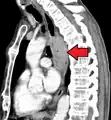

Additional testing is needed to assess how much the cancer has spread (see § Staging, below). Computed tomography (CT) of the chest, abdomen and pelvis can evaluate whether the cancer has spread to adjacent tissues or distant organs (especially liver and lymph nodes). The sensitivity of a CT scan is limited by its ability to detect masses (e.g. enlarged lymph nodes or involved organs) generally larger than 1 cm.[44][45] Positron emission tomography is also used to estimate the extent of the disease and is regarded as more precise than CT alone.[46] PET/MR as a novel modality has shown promising results in preoperative staging with fair feasibility and good correlation in comparison to PET/CT. It can enhance tissue differentiation with lowering the radiation dose to the patient.[47] Esophageal endoscopic ultrasound can provide staging information regarding the level of tumor invasion, and possible spread to regional lymph nodes.

Endoscopy and radial endoscopic ultrasound images of a submucosal tumor in the central portion of the esophagus- Contrast CT scan showing an esophageal tumor (axial view)

- Contrast CT scan showing an esophageal tumor (coronal view)